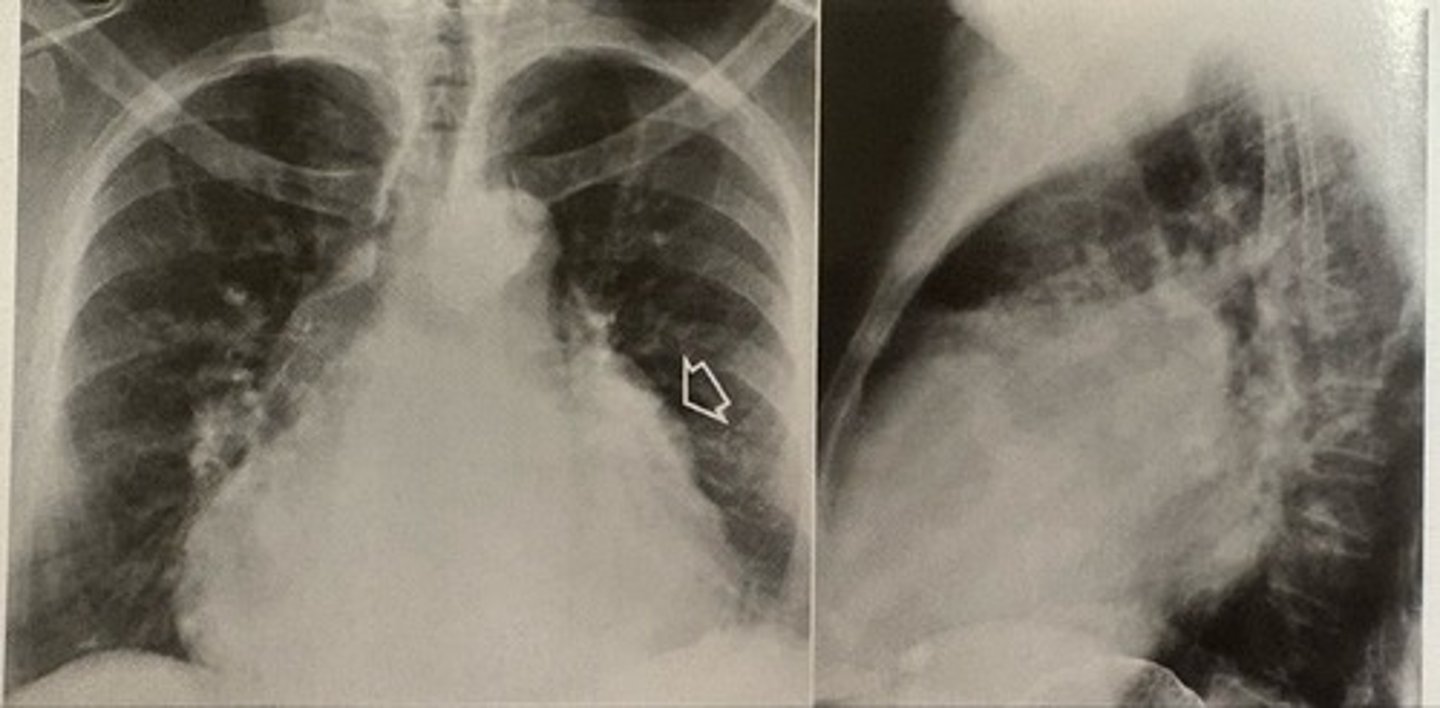

left sided heart failure

what pathology is present?